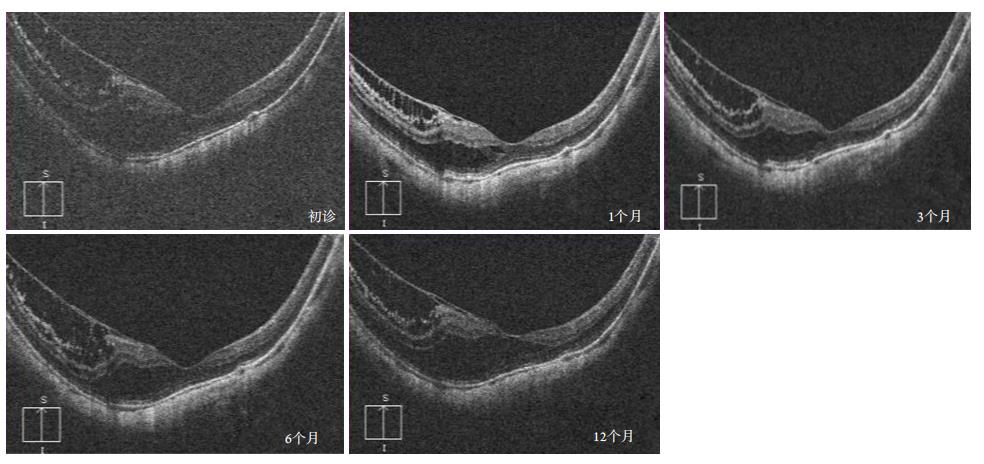

2.4 两组黄斑形态学变化比较

实验组16例16眼T1,1例1眼T2,1例1眼T3,术后随访12个月黄斑形态均未发生改变(图2)。对照组18例18眼T1,12个月随访中1例1眼发展成局限性中心凹脱离(T3),余患者黄斑形态稳定。所有患者均未观察到黄斑裂孔,孔源性视网膜脱离的形成。两组患者黄斑劈裂病程进展率的差异无统计学意义(P=1.00,表6)。

图2 一名男性患者术前黄斑形态(T2),术后随访黄斑形态未发生改变

Figure 2 Preoperative macula morphology of a male patient (T2), and the postoperative macula morphology did not change during the follow-up at 1, 3, 5 and 12 months